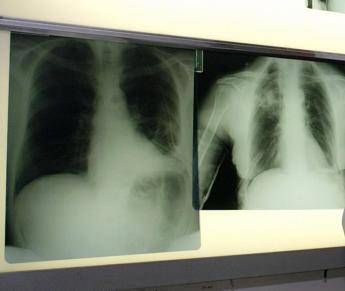

(Adnkronos) – La triplice terapia con budesonide/glicopirronio/formoterolo fumarato (Bgf), già autorizzata per il trattamento della broncopneumopatia cronica ostruttiva (Bpco) negli adulti, ha ricevuto parere positivo dal Comitato per i medicinali per uso umano (Chmp) dell'Agenzia europea per i medicinali (Ema) per l'utilizzo nell'Unione europea di un propellente innovativo di nuova generazione con un potenziale di riscaldamento globale (Gwp) prossimo allo zero. La triplice terapia con budesonide/glicopirronio/formoterolo fumarato è il primo farmaco somministrato tramite inalatore predosato pressurizzato (pMdi) a utilizzare un propellente green, con un potenziale di riscaldamento globale inferiore del 99,9% rispetto ai propellenti attualmente utilizzati nei farmaci inalatori. Questa triplice terapia a combinazione fissa avrà ora un impatto ambientale in termini di emissioni di carbonio comparabile a quella dei farmaci inalatori che non necessitano di propellente.

Il parere positivo del Chmp si basa sui risultati del programma di sviluppo clinico condotto con propellente di nuova generazione, che ha dimostrato la bioequivalenza tra la triplice terapia Bgf con il propellente di nuova generazione e con l'attuale propellente. Il profilo di sicurezza e tollerabilità della triplice terapia a combinazione fissa con il propellente di nuova generazione è risultato coerente con quello già noto del farmaco. "Le malattie respiratorie croniche, tra cui la Bpco e l'asma, sono patologie complesse che impattano fortemente sulla qualità di vita dei pazienti – afferma Federico Lavorini, professore ordinario di Medicina respiratoria dell'Università degli Studi di Firenze – I farmaci respiratori somministrati tramite inalatori predosati pressurizzati, che rappresentano il 76% dell'utilizzo di inalatori a livello globale, sono fondamentali per milioni di persone affette da queste patologie in Italia e in Europa, incluse popolazioni vulnerabili come anziani e bambini. Il parere positivo del Chmp sulla transizione della triplice terapia con budesonide/glicopirronio/formoterolo fumarato verso l'uso di un nuovo propellente a impatto ambientale prossimo allo zero, mantenendo la stessa efficacia e sicurezza, rappresenta un passo importante. Questa decisione garantirà la continuità delle cure per i pazienti, permettendo agli operatori sanitari di scegliere la terapia in base alle esigenze cliniche, contribuendo allo stesso tempo a ridurre l'impatto ambientale". Il parere positivo del Chmp "per la transizione della triplice terapia con budesonide/glicopirronio/formoterolo fumarato al propellente di nuova generazione – commenta Ruud Dobber, Executive Vice President, BioPharmaceuticals Business Unit, AstraZeneca – ci consente di rispondere sia ai bisogni dei pazienti sia a quelli del pianeta e rappresenta una tappa significativa dell'impegno di AstraZeneca a offrire innovazioni per una sanità sostenibile in Europa. A partire dalla triplice terapia con budesonide/glicopirronio/formoterolo fumarato, la transizione al propellente con un potenziale di riscaldamento globale prossimo allo zero su tutta la linea dei nostri farmaci inalatori predosati pressurizzati rappresenta un passo fondamentale verso il raggiungimento della nostra strategia Ambition Zero Carbon". Come sottolinea Susanna Palkonen, Director of the European Federation of Allergy and Airways Diseases Patients' Associations (Efa), "la Bpco è una patologia dall'elevato impatto e rappresenta la terza causa di morte a livello globale. Le persone affette da Bpco – sottolinea – hanno bisogno di avere accesso alla terapia più appropriata, così come a un ambiente sano e ad aria pulita. Accogliamo con favore il parere positivo espresso dal Chmp riguardo ai farmaci inalatori per le vie respiratorie che utilizzano il propellente di nuova generazione, che presenta una significativa riduzione dell’impatto ambientale in termini di emissioni di carbonio". La triplice terapia a combinazione fissa Bgf con il propellente di nuova generazione ha ottenuto la sua prima approvazione nel Regno Unito a maggio 2025, mentre richieste di autorizzazione da parte delle autorità regolatorie sono attualmente in corso anche in Cina e in altri Paesi, riporta la nota. Si tratta del primo farmaco nel portfolio di AstraZeneca di terapie inalatorie somministrate tramite pMdi a passare al nuovo propellente. La farmaceutica fa sapere che ambisce a convertire l'intero portfolio di farmaci somministrati tramite pMdi al propellente con un Gwp prossimo allo zero entro il 2030, nell'ambito della strategia Ambition Zero Carbon. In Europa, l'avvio della transizione della triplice terapia a combinazione fissa al nuovo propellente è previsto nei prossimi mesi. Le malattie respiratorie croniche, tra cui la Bpco e l'asma – ricorda AstraZeneca – colpiscono centinaia di milioni di persone a livello globale. I farmaci inalatori respiratori somministrati tramite pMdi rappresentano il 76% dell'utilizzo di inalatori a livello globale e contribuiscono per lo 0,04% alle emissioni globali di gas serra. Gli studi dimostrano che il maggiore impatto ambientale associato alle malattie respiratorie deriva dal mancato controllo della patologia e dal conseguente aumento della necessità di ricorrere a servizi sanitari. L'implementazione di linee guida basate sulla generazione di evidenze nella pratica clinica può contribuire a ridurre le riacutizzazioni e i ricoveri ospedalieri, migliorare gli outcome per i pazienti e anche diminuire l'impatto delle emissioni di carbonio complessive associate alle cure respiratorie. —salutewebinfo@adnkronos.com (Web Info)